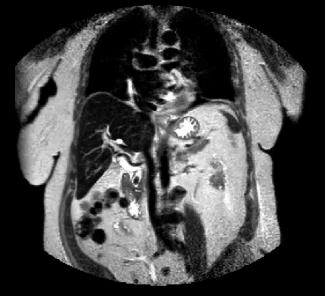

These are both MR images. The image on the left is a coronal T2-weighted sequence, with bright fat and high signal fluid in the stomach and biliary system. The image on the right is a 3D reconstruction that just shows the biliary system, an MRCP. Both studies show a dilated biliary tree and a low signal lesion in the distal CBD consistent with a stone. MR is usually not the first study done in patients with jaundice, but can be very useful in complex cases where US or CT do not give a clear diagnosis.